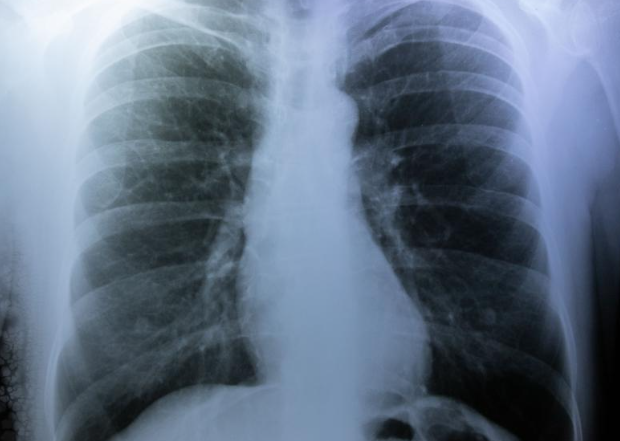

기흉이 발생하면 병원에서 적절한 치료를 받는 것이 중요합니다. 경미한 기흉의 경우 산소 치료와 함께 자연적으로 회복될 수 있습니다. 이 경우 회복 기간은 대개 1-2주 정도입니다. 그러나 심한 기흉은 흉관 삽입술이나 흉강경 수술(VATS)이 필요할 수 있습니다. 이러한 수술 후 초기 회복 기간은 대개 3-7일 정도입니다. 병원에서는 환자의 상태를 모니터링하고, 흉부 X-ray 등을 통해 폐의 재확장 여부를 확인합니다. 초기 회복 단계에서는 환자가 무리한 움직임을 피하고, 충분한 휴식을 취하는 것이 중요합니다.